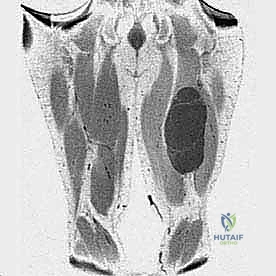

1. التصوير بالرنين المغناطيسي (MRI)

يُعد الرنين المغناطيسي بالصبغة المعيار الذهبي (Gold Standard) لتشخيص أورام الأنسجة الرخوة. يوفر صوراً ثلاثية الأبعاد وعالية الدقة تفصل الورم عن العضلات السليمة، وتوضح بدقة متناهية علاقة الورم بالعصب الوركي والأوعية الدموية الرئيسية (الشريان والوريد الفخذي العميق).

2. التصوير المقطعي المحوسب (CT Scan) للصدر

نظراً لأن ساركوما الأنسجة الرخوة تميل إلى الانتشار (الانبثاث) إلى الرئتين أولاً عبر مجرى الدم، فإن إجراء أشعة مقطعية للصدر أمر إلزامي لتحديد مرحلة المرض (Staging) والتأكد من عدم وجود نقائل رئوية.